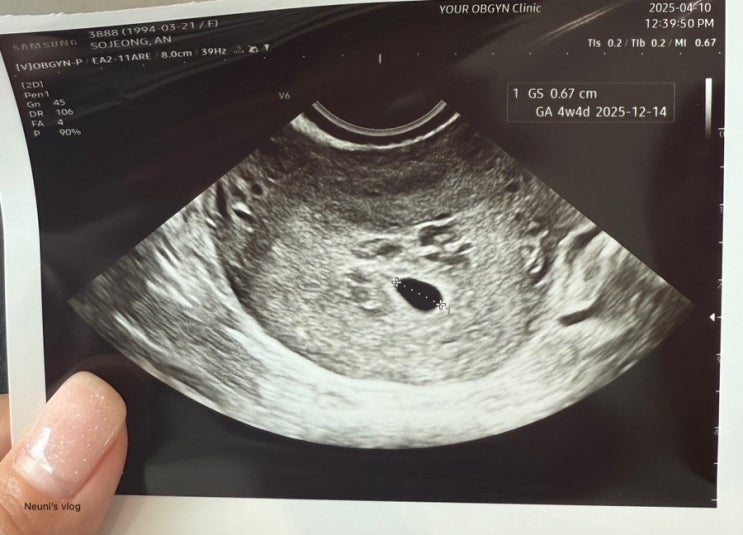

[엄마되기] 임신확인부터 5주차까지 기록

처음에 임신준비를 하면서 모든 신혼 부부들이 하는 착각을 우리부부도 하고 있었다 ‘피임을 안하면 임신...